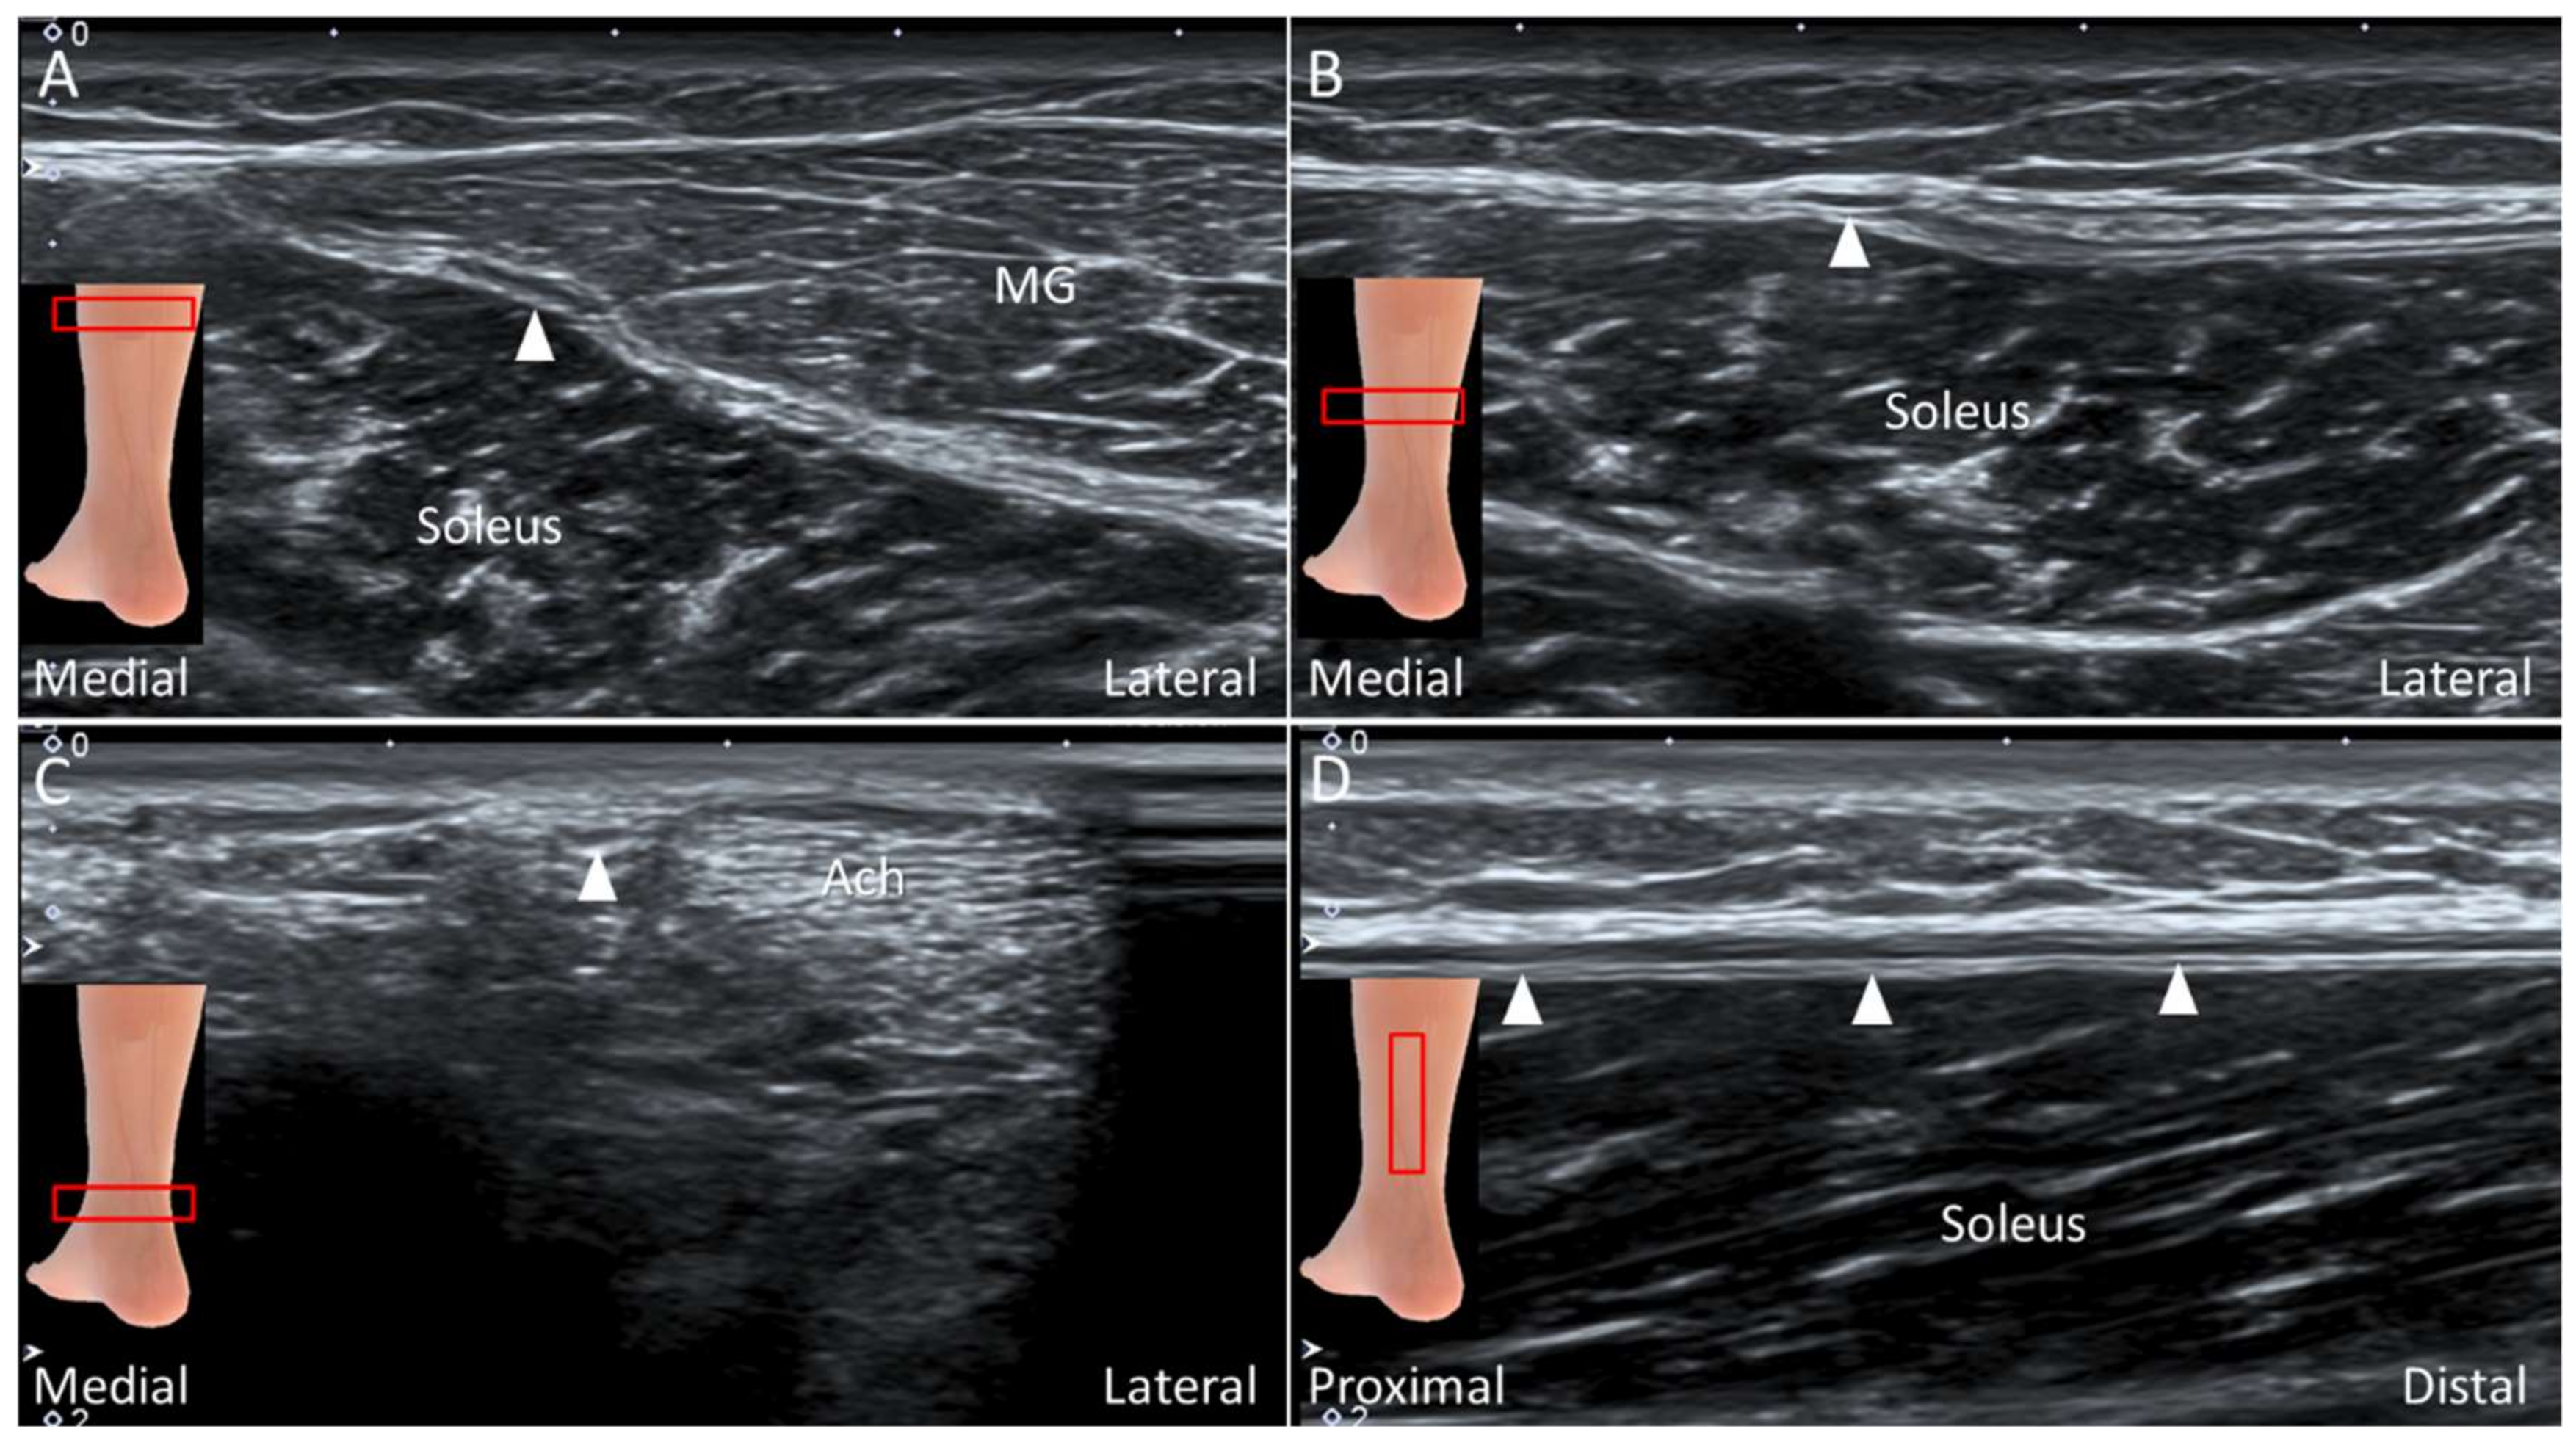

4.4. Plantaris Tendon

4.4.1. Anatomy

4.4.2. Scanning Technique

4.4.3. Clinical Relevance